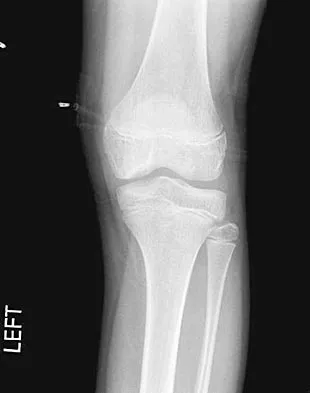

A 28-year-old professional football player reports painless loss of ankle motion after sustaining a "severe" ankle sprain 12 months ago. A mortise radiograph is shown in Figure 1. Surgical treatment should be reserved for which of the following conditions?